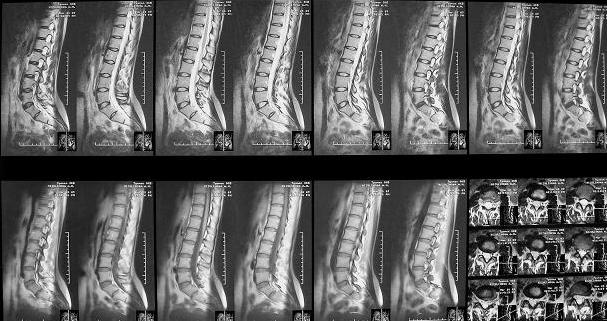

Здравствуйте уважаемые коллеги. Высылаю обещаннное ЯМРТ. Никаких нарушений м\позвонковых дисков, мяггкотканных образований на уровне Th12-S3 не обнаружено.